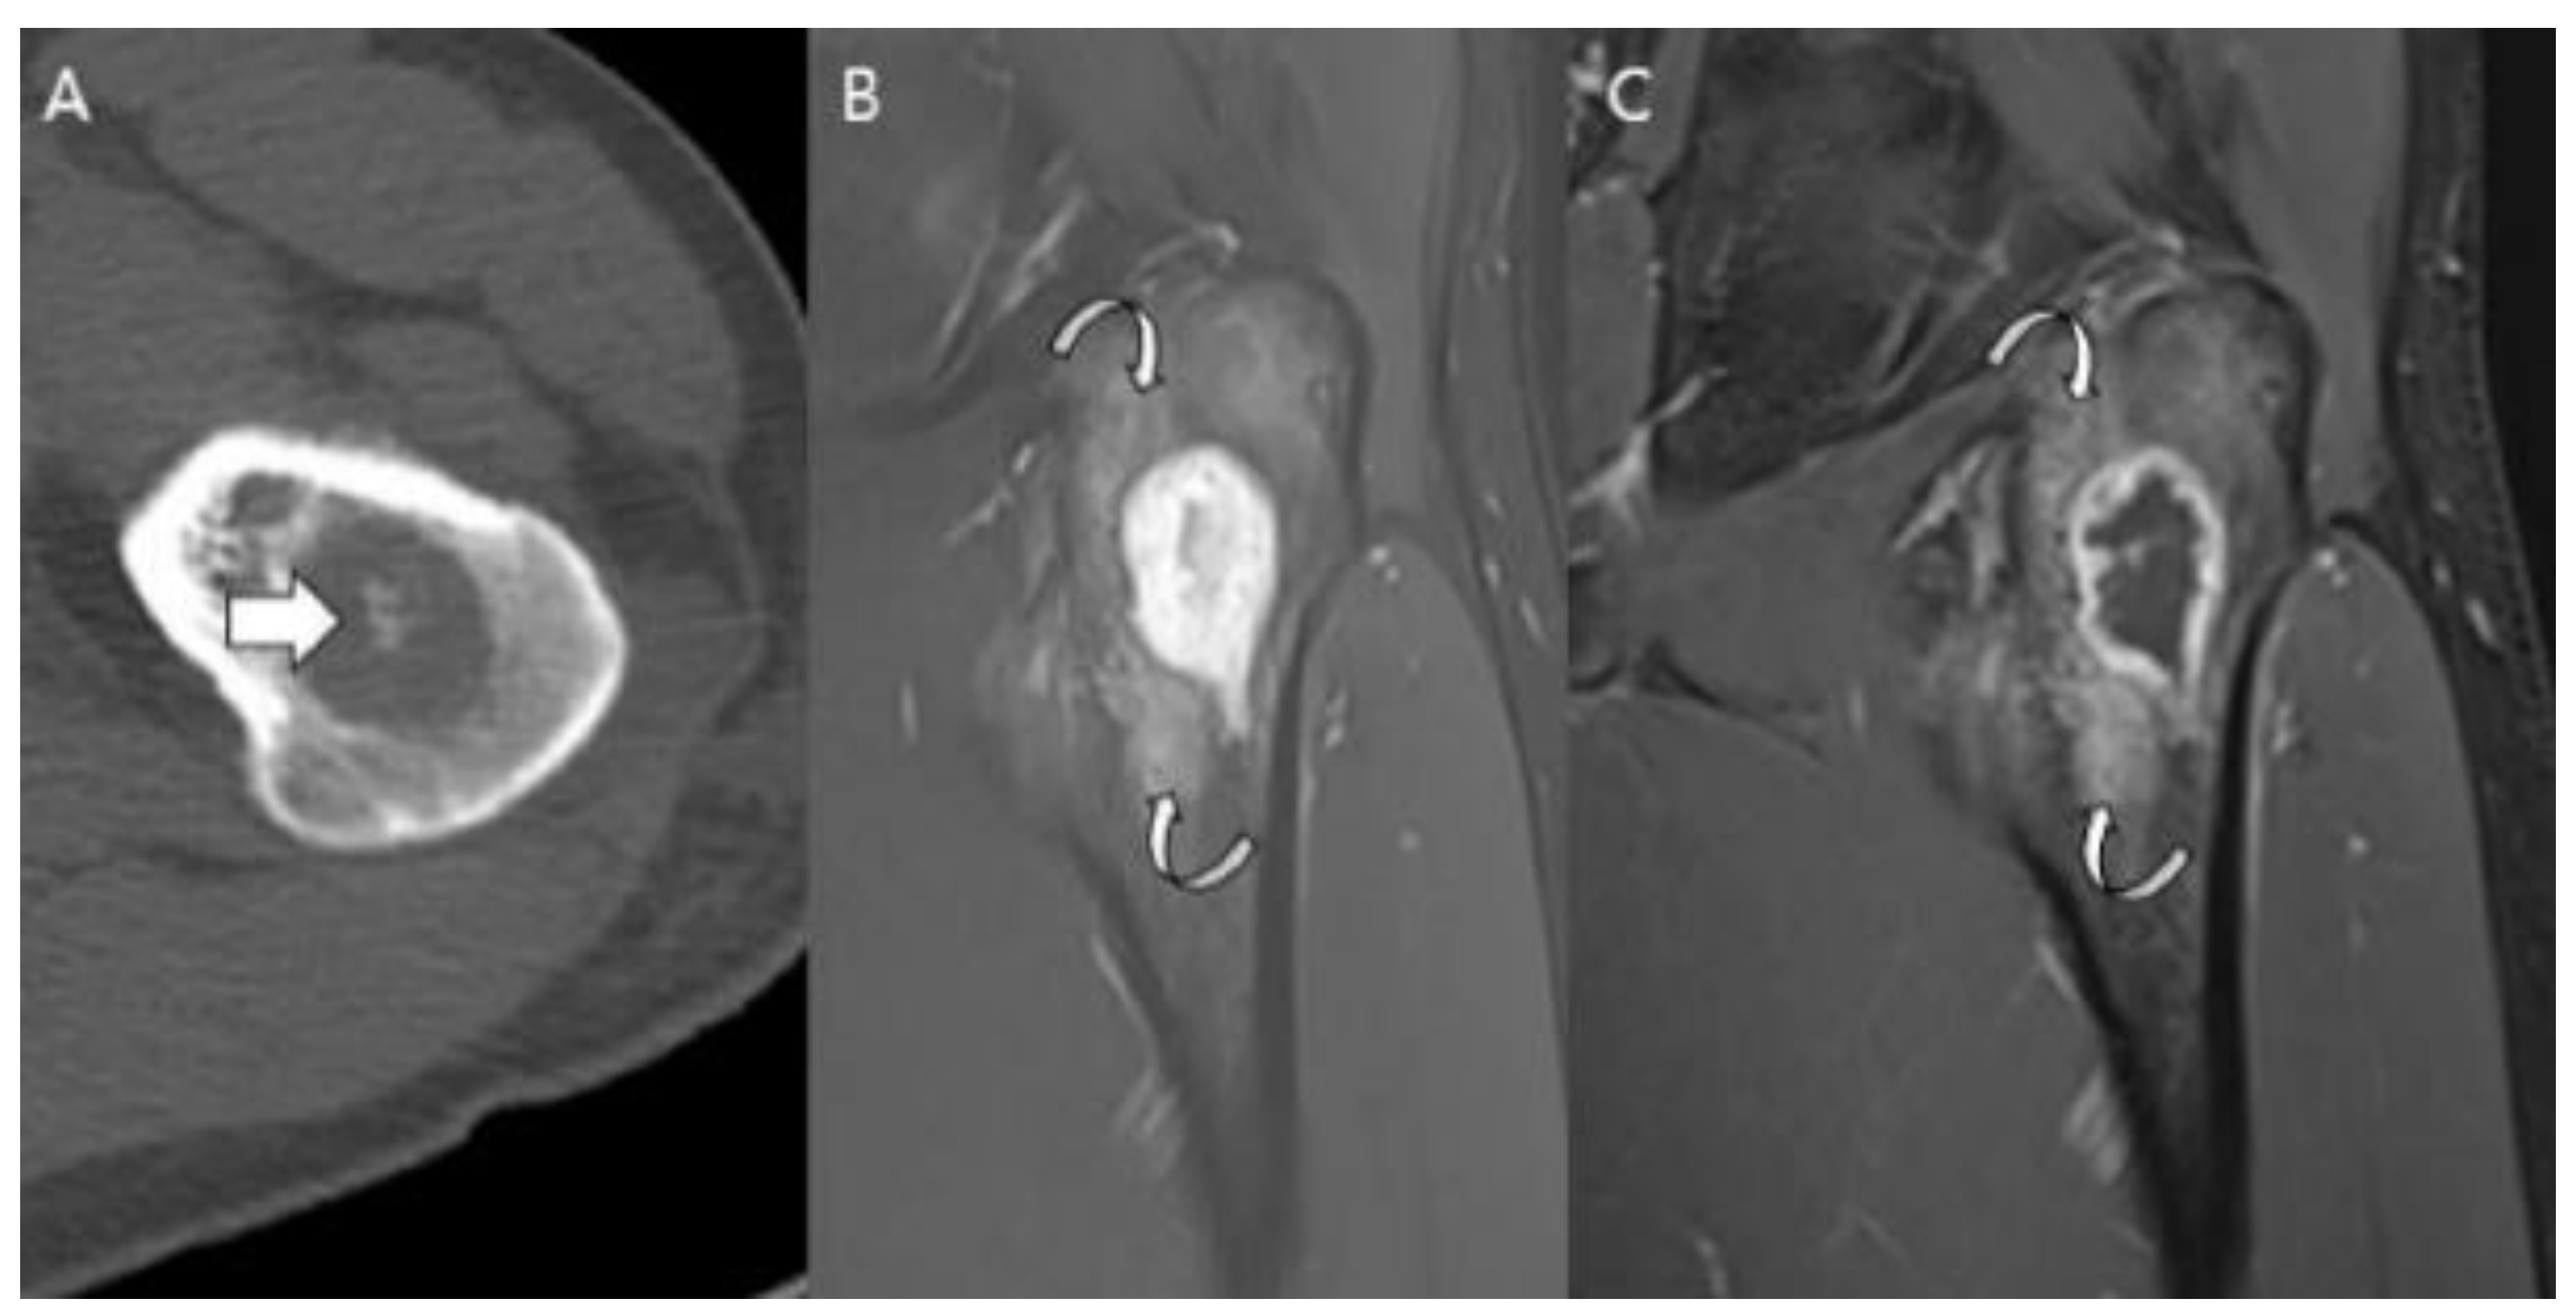

- Collins, M.S.; Koyama, T.; Swee, R.G.; Inwards, C.Y. Clear cell chondrosarcoma: Radiographic, computed tomographic, and magnetic resonance findings in 34 patients with pathologic correlation. Skelet. Radiol. 2003, 32, 687–694. [Google Scholar] [CrossRef]

- Kumar, R.; David, R.; Cierney, G., 3rd. Clear cell chondrosarcoma. Radiology 1985, 154, 45–48. [Google Scholar] [CrossRef]

- Bagley, L.; Kneeland, J.B.; Dalinka, M.K.; Bullough, P.; Brooks, J. Unusual behavior of clear cell chondrosarcoma. Skelet. Radiol. 1993, 22, 279–282. [Google Scholar] [CrossRef]

- PPresent, D.; Bacchini, P.; Pignatti, G.; Picci, P.; Bertoni, F.; Campanacci, M. Clear cell chondrosarcoma of bone. Skelet. Radiol. 1991, 20, 187–191. [Google Scholar] [CrossRef] [PubMed]